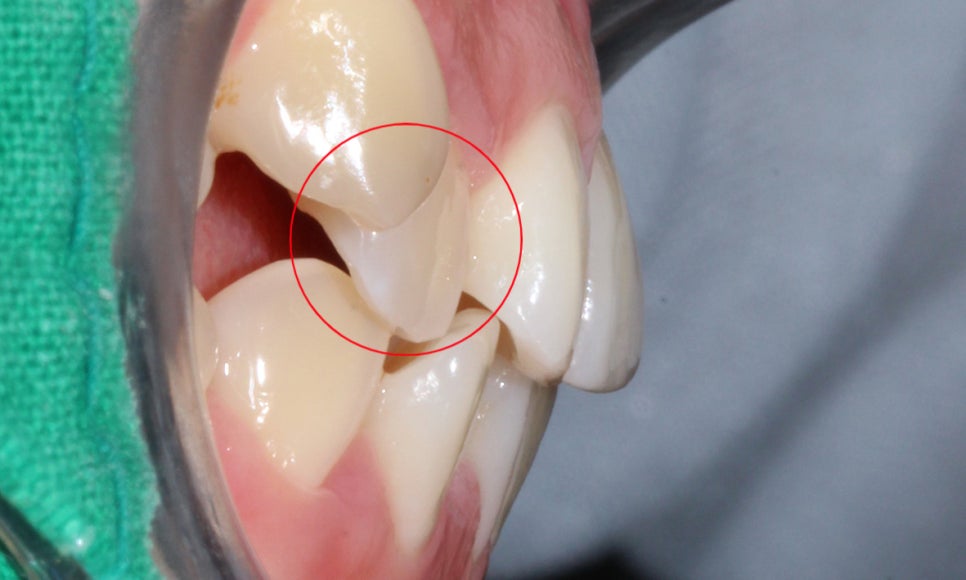

전치부의 측면 사진을 보시면

전치부 치아의 크라우딩으로 인해

안모가 약간 돌출되어 보이는 모습으로

송곳니덧니 증상으로 인해 상악의

측절치가 크게 삐뚤어진 모습인데요,

측절치가 이상적인 안모의 형태를

갖추지 못하고 치아 안쪽으로 뻐드러진 모습입니다.